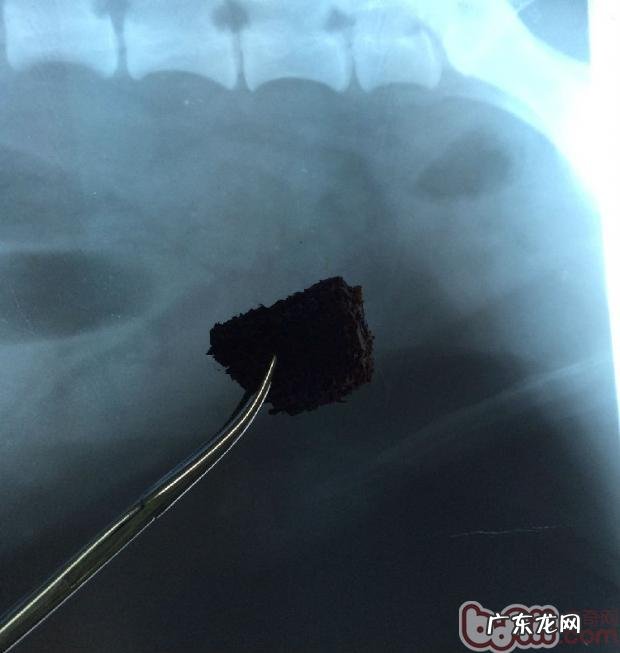

取下物为三乘四厘米大的玉米棒子 , 早已呈灰黑色 , 上边还沾有刮伤肠胃粘膜的印痕 , 可能在肠胃内存储的時间早已超出一周的時间下面的图是取下物与X线片比照下的照片 。

取下物与X线片比照下的照片 。